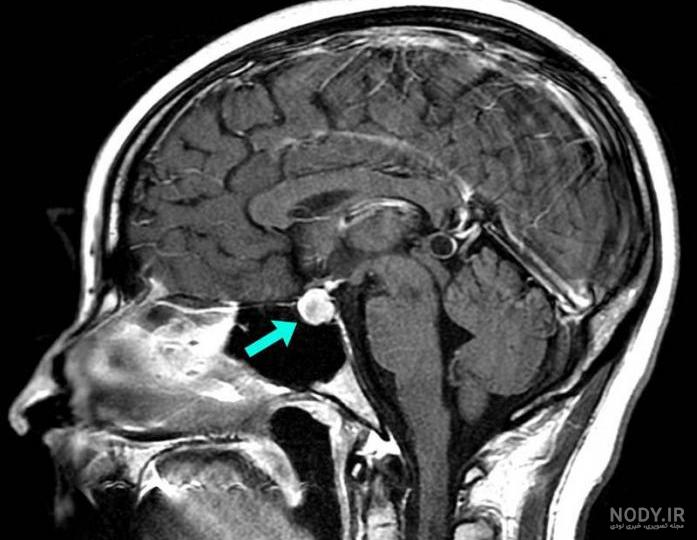

نوبت دهی ام آر آی هیپوفیز (مغز) با تزریق چگونه است و چرا انجام میشود؟

تصویربرداری

نوبت دهی ام آر آی هیپوفیز (مغز) با تزریق چگونه است و چرا انج...

1404/11/19

برای بررسی وجود تومورهای هیپوفیز (آدنوم های هیپوفیز) که ممکن است باعث مشکلات هورمونی شوند، استفاده می شود. ۲. بر...